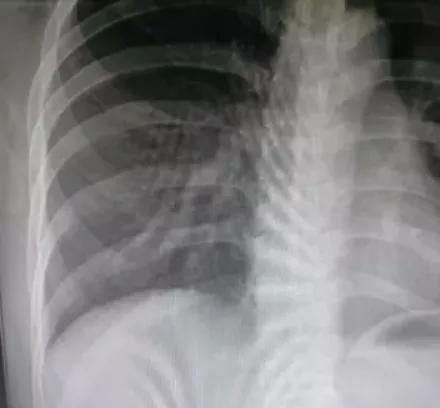

正常呼吸拍摄(同比例局部放大)

深吸气后屏气拍摄(同比例局部放大)